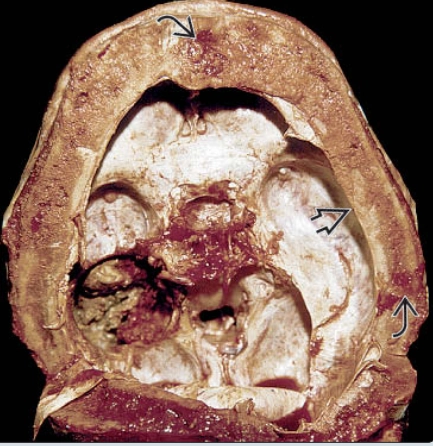

• Bệnh Paget xương sọ - Paget disease (skull)